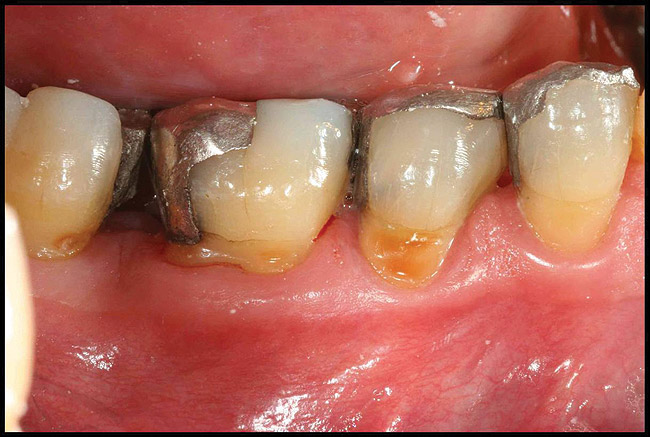

After complete management of moderate to severe periodontitis, including scaling and root planing and in some cases periodontal surgery, subsequent regular periodontal maintenance is reported to prevent tooth loss in up to 85% of patients over a long-term follow-up interval of up to 53 years.6,8 This high success rate of periodontal treatment is comparable to that of dental implants in replacing teeth lost to severe periodontal diseases, highlighting the predictability of maintaining the natural dentition in most patients with periodontal diseases9,10 (Figure 1A and Figure 1B).

Figure 1a  Long-term results of a case involving a 55-year-old woman treated by regenerative periodontal surgery followed by periodontal maintenance every 3 months for 8 years. (A) Radiograph taken in May 2000

Figure 1a

Figure 1b  Long-term results of a case involving a 55-year-old woman treated by regenerative periodontal surgery followed by periodontal maintenance every 3 months for 8 years. (B) radiograph of the same area taken in July 2008.</a></span><P>Figure 1b</P></div>    <div class=